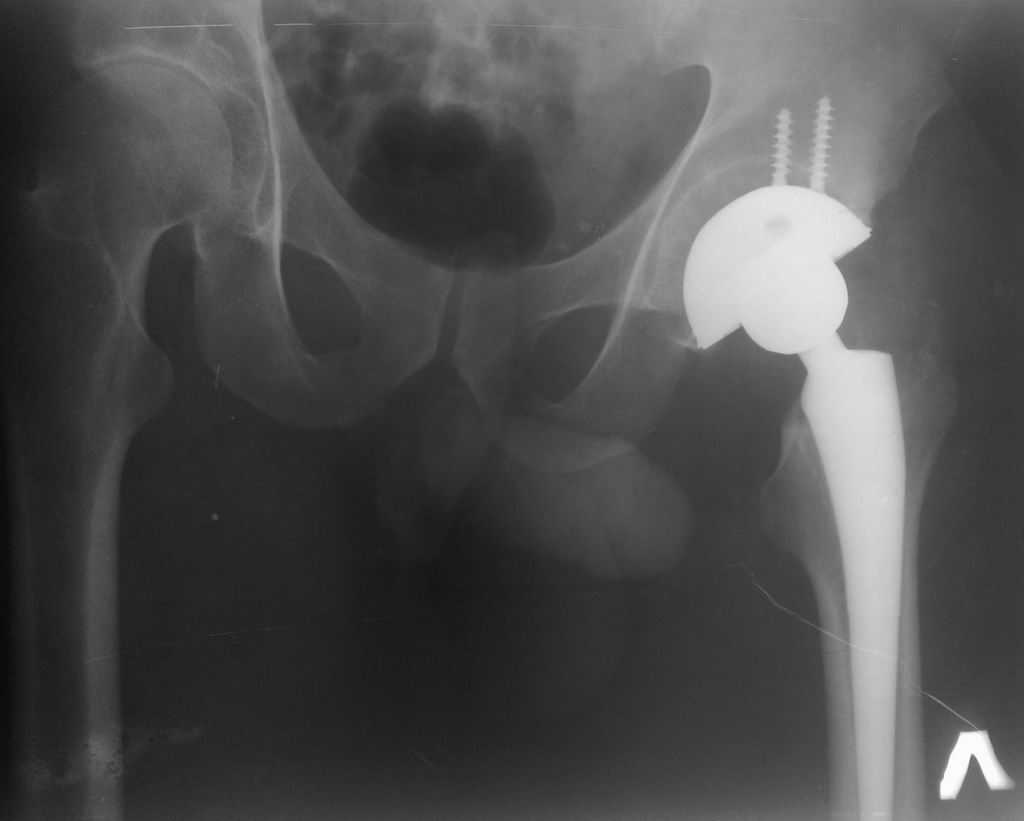

Уважаемый Станислав! Впадина недоработана, антеверзии нет, можно было на размер меньше взять тазовый компонент. Если заднего вывиха не произойдет, может все обойдется.

Какой доступ использовали? Насколько он был травматичен? Я бы дождался полного заживления раны и через пару месяцев выполнил ревизию с заменой чашки, вкладыша и, скорее всего, головки. По снимку похоже что установлена короткая головка, после переустановки чашки в правильную позицию, скорее всего, потребуется стандартная или даже плюсовая.

Доступ по Хардингу. Головка действительно S.

Чашка конечно же Variocup(Varioloc - ножка). После "погружения" чашки головку скорее всего придется менять на M или L.

Ситуация неоднозначная, сколько специалистов, столько и мнений. Выскажу свое на основании нескольких подобных же ситуаций. Если во время установки Вы получили достаточно плотное заклинивание чашки в ВВ, плюс к этому усилили фиксацию 2-я винтами, которые так же встали плотно, то ничего страшного не происходит. Мы ведь нередко пользуемся при ревизии приемом, когда центральный дефект пластируем стружкой и вся надежда на фиксацию чашки в "риме". Если же этого пресс-фит эффекта Вы не получили и лишь "прикрутили" чашку винтами, тогда нет смысла ждать, надо исправлять ситуацию.

Уважаемый Рашид Муртузалиевич! Чашка поставлена плотно даже без винтов. Пациент достаточно активного образа жизни, есть опасения, что чашку раскачает через непродолжительное время (несколько месяцев). Про прочие проблемы, помимо чисто медицинских я уже упомянул. Для себя мы уже решили идти на ревизию, спланировали ход вмешательства, проиграли различные нештатные ситуации, подготовили соответствующий инструмен и импланты. С больным все обговорено - все риски и возможные осложнения. Достигнуто, я надеюсь взаимопонимание. Всем спасибо! Операцию запланировали на будущий вторник. Сообщу о результатах.

Уважаемый Ильдар Фуатович! Диаметр головки 32 мм. Жалоб со стороны пациента ПОКА нет. После операции срок никакой, пациент практически не начал нагрузку на оперированную конечность(только "весом конечности"). Повторюсь, что чашка стоит стабильно, в принципе можно было обойтись и без винтов. Сомнения в плане "недогруза" чашки были во время операции - пальпацией зондом через центральное отверстие, но, как говорится, "бес попутал".

Если вы выполнили импакционную пластику "дна" - то волноваться особо не стоит (разве, что чашка поставлена несколько вертикально, что чревато чрезмерным износом полиэтилена), если нет, то риск асептического расшатывания очень велик, т.к. при диастазе между чашкой и костью в 2-3 мм расcчитывать на ongrowth, тем более на ingrowth не приходится. Если случился вариант 2, я бы выполнил ревизию в принятые для вашей конторы сроки (наверное после снятия швов и чистой коже), честно поговорив перед этим с пациентом.

Максим,спасибо за ответ. Между чашкой и дном - пустота. Фиксация только по краю и на винтах. Я считаю, что при нагрузке все очень быстро "развалится". Спрашиваю так настойчиво, ибо с такой ситуацией столкнулся впервые. Собственно, решение уже принято, с больным беседа проведена. На следующей неделе попытаемся взять на ревизию.

Хотелось бы увидеть рентгенограмму до имплантации. Погружение достаточное, хороший контакт с костным ложем. Центр вращения сустава сохранен. Мне кажется выбрана большая "чашка". Во всяком случае - не стоит ничего менять. Канзюба А.И.

Сегодня все-таки выполнили ревизию вертлужного компонента. Действительно, чашка держалась только по окружности, относительно легко удалилась. Так что тактику считаю правильной, ибо ловить при такой установке особо нечего было. Нестабильность в блишайшее время была бы обеспечена. Снимки после переустановки в приложении. Качество, конечно не ахти какое, это сделано на столе на плохом аппарате. Посадка проконтролирована визуально через центральное отверстие. Головку не снимали, оставили короткую. Если до ревизии длина левой ноги была +1 см, то после D=S. Теперь осталось молиться, чтобы не было осложнений. Вроде бы все прошло не травматично.